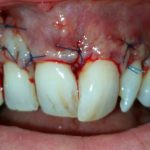

Traumatisme avec perte des 2 incisives centrales (2005)

Les deux incisives ne sont plus réimplantables

Deux implants et les couronnes céramiques, image radiologique

Deux couronnes sur implants. Notez l’architecture optimale festonnée de la gencive